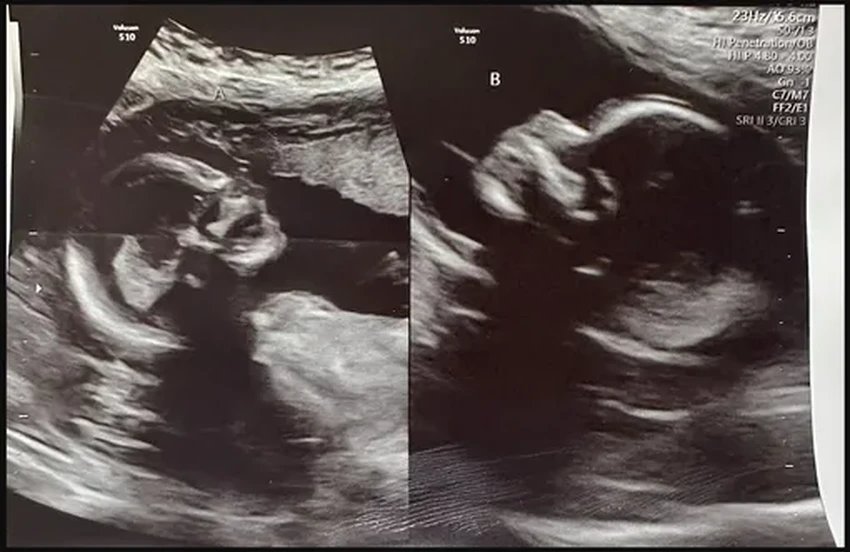

Келси жила с этой особенностью, даже не подозревая о ней, пока в 17 лет врачи не поставили диагноз. И вот теперь, будучи мамой троих прекрасных детей (7, 4 и 2 лет), она готовится к рождению еще двоих. Любопытно, что все предыдущие беременности протекали в одной матке — природа будто решила на этот раз «включить» и вторую.

Шансы на такое событие астрономически малы — примерно 1 к 50 миллионам. Последний раз мир наблюдал подобное в 2019 году в Бангладеш, где между рождением «двойняшек» прошло целых 26 дней. Вот уж действительно, каждый ребенок решил появиться в свой особенный день.